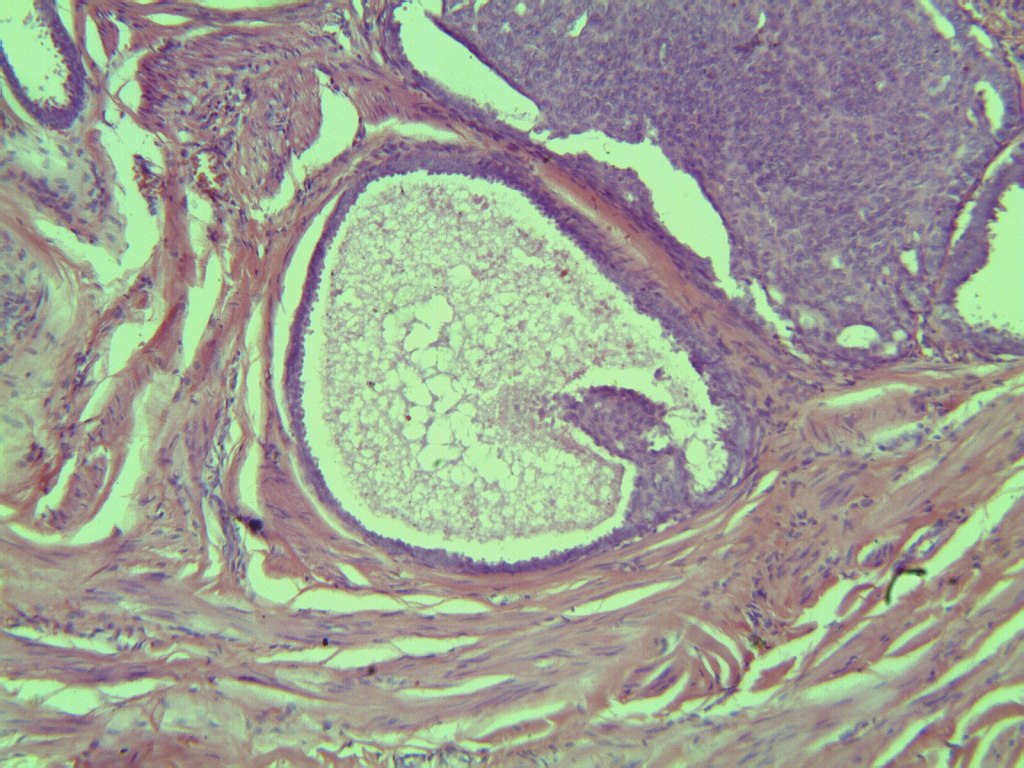

H&E Breast Slide H&E Breast Slide H&E Breast Slide

The nuclear pleomorphism and mitotic activity suggest Grade 2 invasive ductal carcinoma. Stromal invasion pattern is clear.

Findings align with Grade 2 invasive ductal carcinoma. Stromal invasion is evident; ER/PR/HER2 testing is recommended.

H&E Breast Slide

Breast H&E